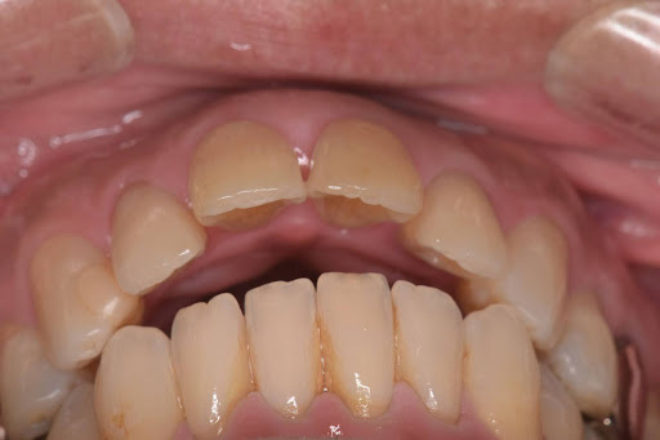

開咬とは、奥歯を噛んだときに上下の前歯の間に隙間ができてしまう状態のことです。

オープンバイトとも呼ばれ、不正咬合の一種に分類されます。

しかし、開咬の場合は、どれだけ奥歯を噛みしめても前歯同士が接触せず、隙間が残ってしまいます。